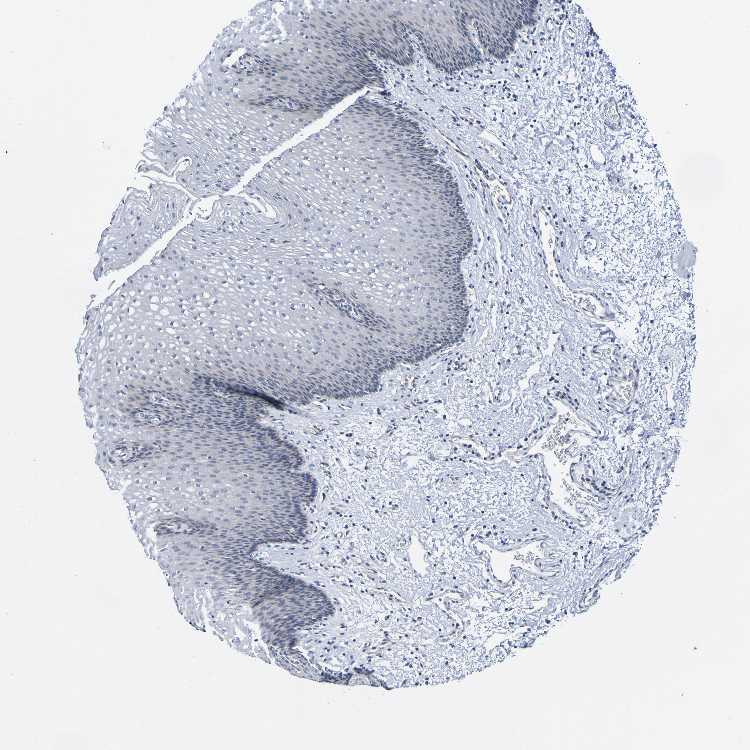

ESOPHAGUS - Antibody stainingi

Antibody staining in the annotated cell types in the current human tissue is reported as not detected, low, medium, or high, based on conventional immunohistochemistry profiling in selected tissues. This score is based on the combination of the staining intensity and fraction of stained cells.

Each image is clickable and will lead to virtual microscopy that enables deeper exploration of all samples and also displays staining intensity scores, fraction scores and subcellular localization as well as patient and tissue information for each sample.

Antibody HPA010972

Squamous epithelial cells Not detected